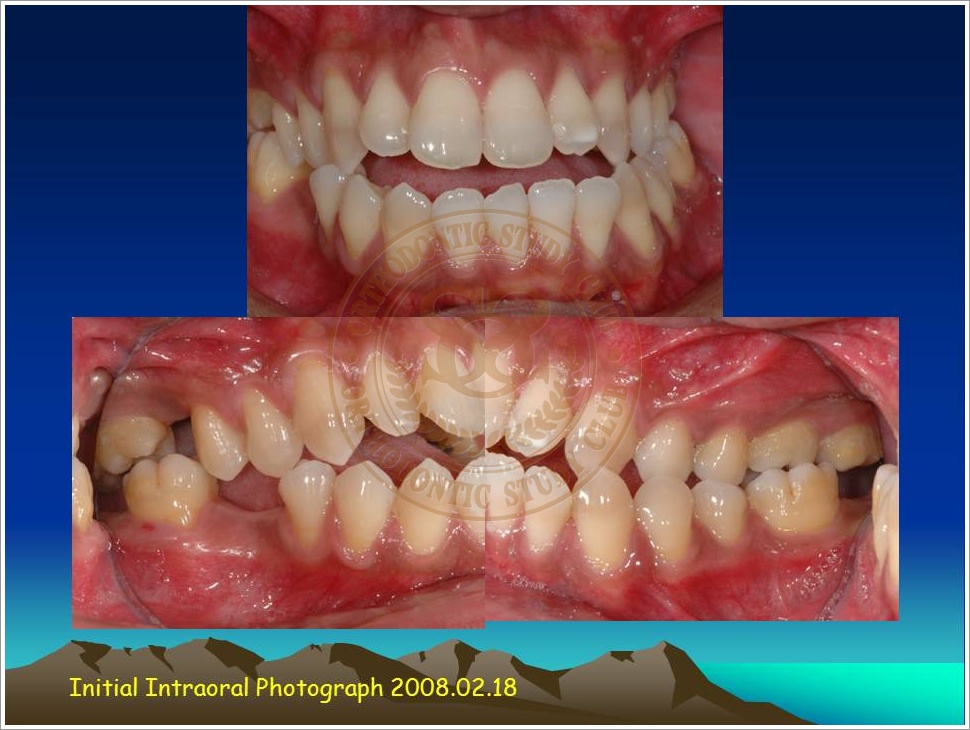

Treatment of Pseudo Class III (Class I Molar Relationship) and management of the embedded maxillary canine (Pt. Miss J.I.)